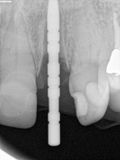

fredlibc | all galleries >> Galleries >> NSankhyan - immediate load 22 > R1.jpg

R1.jpg